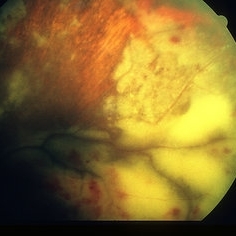

AIDS - Toxoplasmosis

Jun 4 2014 by Henry J. Kaplan, MD

Fundus photograph of a patient with AIDS who has developed toxoplasma retinochoroiditis; large yellow patch of retinitis along the superior arcade fading the vasculature with feathery edges. #1

Condition/keywords: AIDS, toxoplasmosis